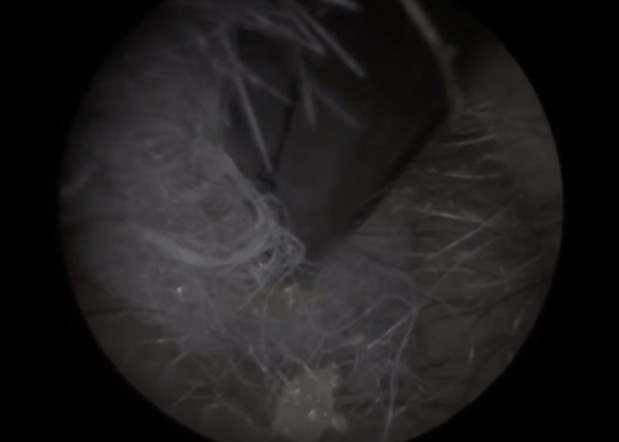

”Vahakuiskaaja” jakoi YouTubeen videon, jossa hän vetää korvan sisälle juuttuneen vanukasan pois potilaan korvasta. Ällöttävä video on kuvattu Leicestershiressa Neel Raithathan klinikalla, joka on erikoistunut kuulotutkimuksiin. Potilas oli käyttänyt korvien puhdistamiseen vanupuikkoa, jonka pää oli irronnut ja jäänyt jumiin korvan sisälle. Neel poisti vanun korvasta, joka oli ehtinyt tulehtua ja muodostamaan nestettä korvan sisälle.

Neel näkee usein tapauksia, joissa vaha on pakkautunut korvakäytävän perälle – syynä on pääosin se että ihmiset luulevat tekevänsä oikein kun he putsaavat korvansa vanupuikkojen avulla.